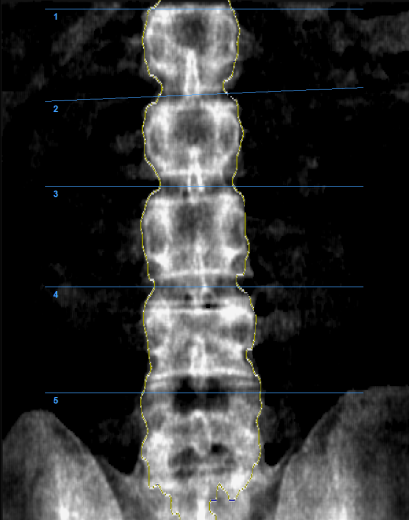

Денситометр InAlyzer-AIR, разработанный компанией Medikors, использует технологию рентгеновского излучения. Он пропускает сфокусированный рентгеновский луч через анализируемый объект – кость. Измеряется степень поглощения рентгеновских лучей, и эта информация используется для расчёта плотности и состава. Эта технология позволяет неинвазивно измерять минеральную плотность костной ткани и может использоваться для точной и достоверной диагностики остеопороза или мониторинга эффективности лечения.

С помощью InAlyzer-AIR можно определить не только минеральную плотность костной ткани, но и процент жировой и мышечной ткани.